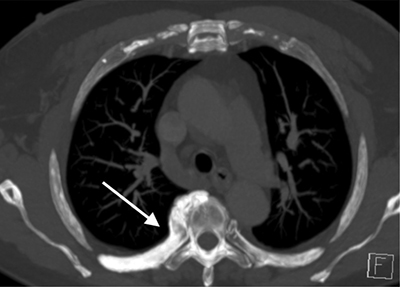

Figure 2A

CT thorax axial MIP images.